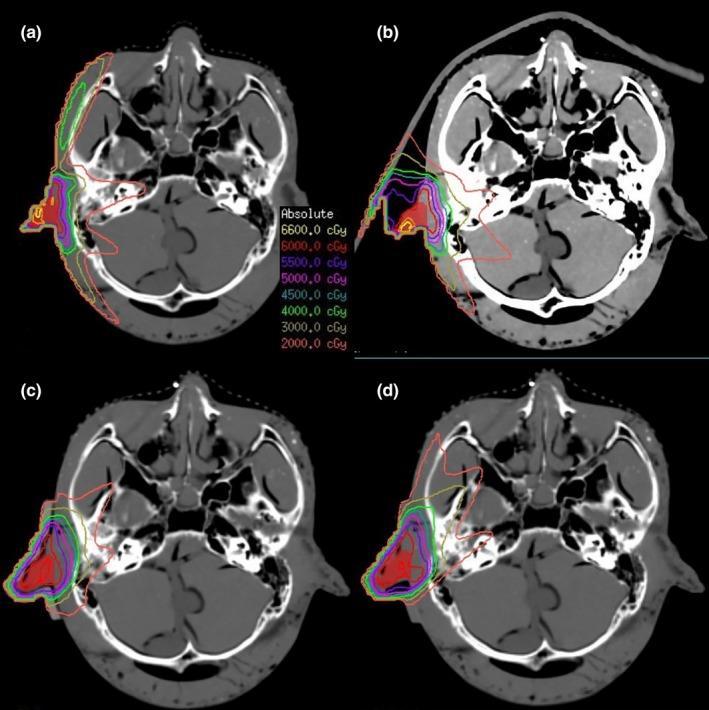

We used 3D printing technology to make silica gel and hydrogel boluses. To evaluate the clinical feasibility, intensity modulated radiation therapy (IMRT) plans were created for head phantoms that were bolus-free or had a commercial bolus, a silica gel bolus, or a hydrogel bolus. Dosimetry differences were compared in simulating nose, ear, and parotid gland radiotherapy separately.

The air gaps were smaller in the silica gel and hydrogel bolus than the commercial one. In nose plans, it was shown that the V (relative volume that is covered by at least 95% of the prescription dose) of the silica gel (99.86%) and hydrogel (99.95%) bolus were better than the commercial one (98.39%) and bolus-free (87.52%). Similarly, the homogeneity index (HI) and conformity index (CI) of the silica gel (0.06; 0.79) and hydrogel (0.058; 0.80) bolus were better than the commercial one (0.094; 0.72) and bolus-free (0.59; 0.53). The parameters of results (HI, CI, V ) were also better in 3D printing boluses than in the commercial bolus or without bolus in ear and parotid plans.